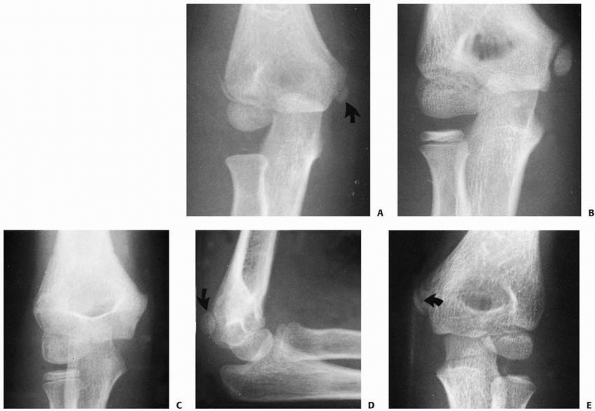

![]() |

FIGURE 15-19 Spur formation. A.

Follow-up radiograph of a boy whose lateral condylar fracture was treated nonoperatively. The periosteal flap produced a spur on the lateral aspect of the metaphysis (arrow). This fracture healed with a mild varus angulation as well. B. Clinically, the spur accentuated the lateral prominence (arrow) of the elbow, which in turn accentuated the mild valgus angulation. C. Considerable soft tissue dissection was performed in the process of open reduction of this lateral condylar fracture. D. At 2 months postsurgery, there is a large irregular spur formation secondary to periosteal new bone formation from the extensive dissection. (From Wilkins KE. Residuals of elbow fractures. Orthop Clin N Am 1990;21:289-312, with permission.) |